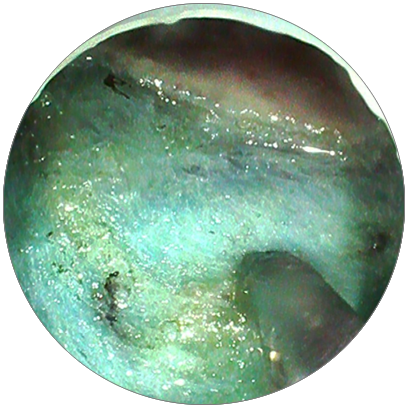

經(jīng)過1個(gè)半小時(shí)的努力

手術(shù)順利完成

術(shù)后

經(jīng)醫(yī)生評(píng)估后

常叔可回家休養(yǎng)